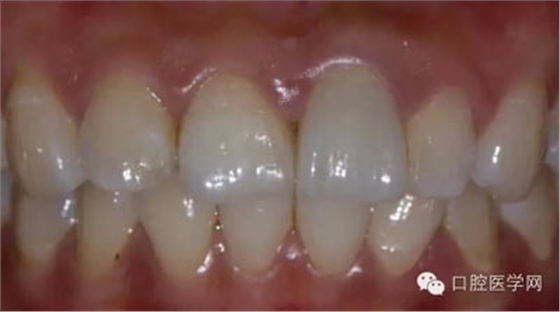

5、3MU200樹脂粘接劑粘固全瓷冠術(shù)后照

6、術(shù)后一周照,牙齦恢復(fù)良好

7、術(shù)后照飽和度調(diào)到最低與最高,觀察牙齒修復(fù)后的明度及飽和度

8、術(shù)前術(shù)后對(duì)比